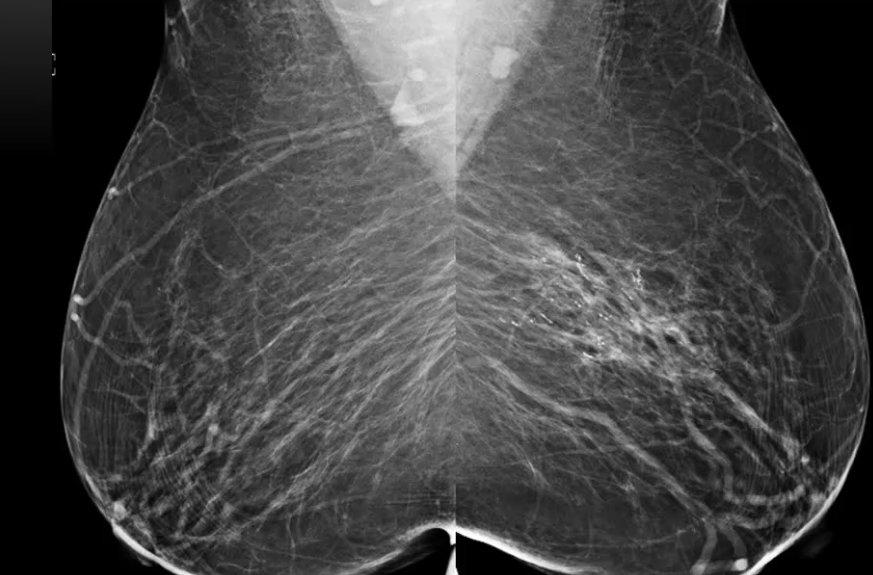

What is this an image of?

Fatty breast tissue

Dense breast tissue - more difficult to see breast cancers